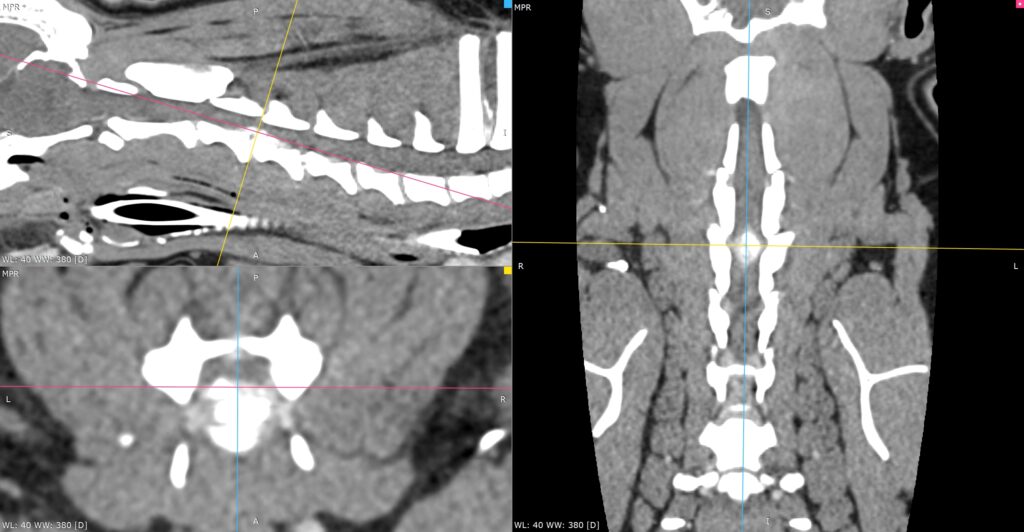

3D_MPR_-_ORION_TOUMIEUX_-_25_07_2025_10_15_34_-_OS_RACHIS_1.0_0000

Discospondylite L6-L7 sur un Setter gordon.